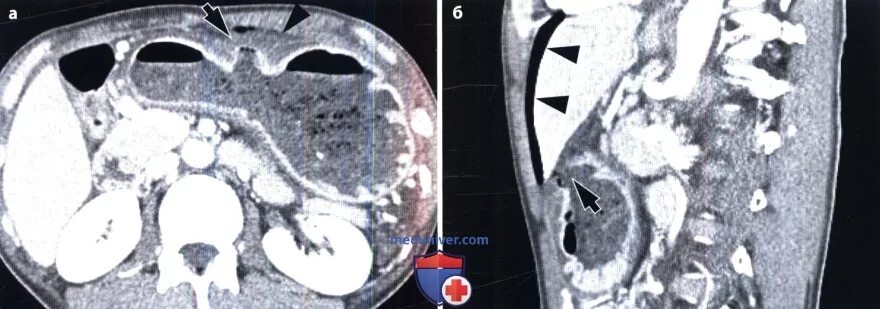

Язва желудка кт